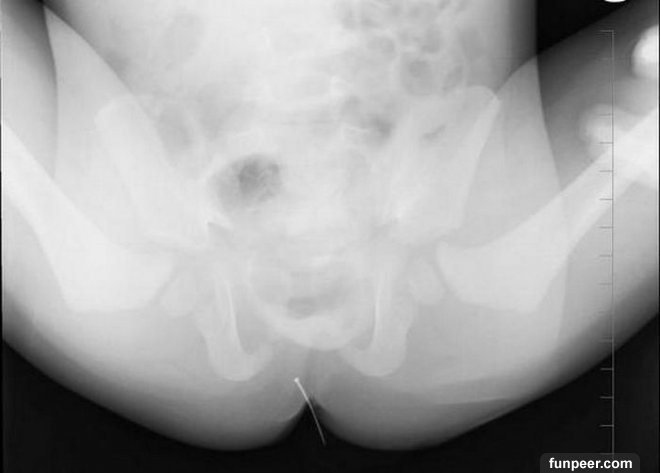

有些男性喜歡用筆桿、稻草稈、髮夾、塑膠絲等物插入尿道,以企求獲得快感。(健康提示:泌尿系有異物,當尿道或膀胱頸梗阻時可造成排尿困難或尿瀦留,並伴泌尿系統感染,最後形成泌尿系統結石症。所以奉勸各位男士千萬不要採用刺激尿道的方法進行自慰。)

【猜一猜】你能從這些X光片中看出他/她們使用的是什麼東西進行自慰嗎?